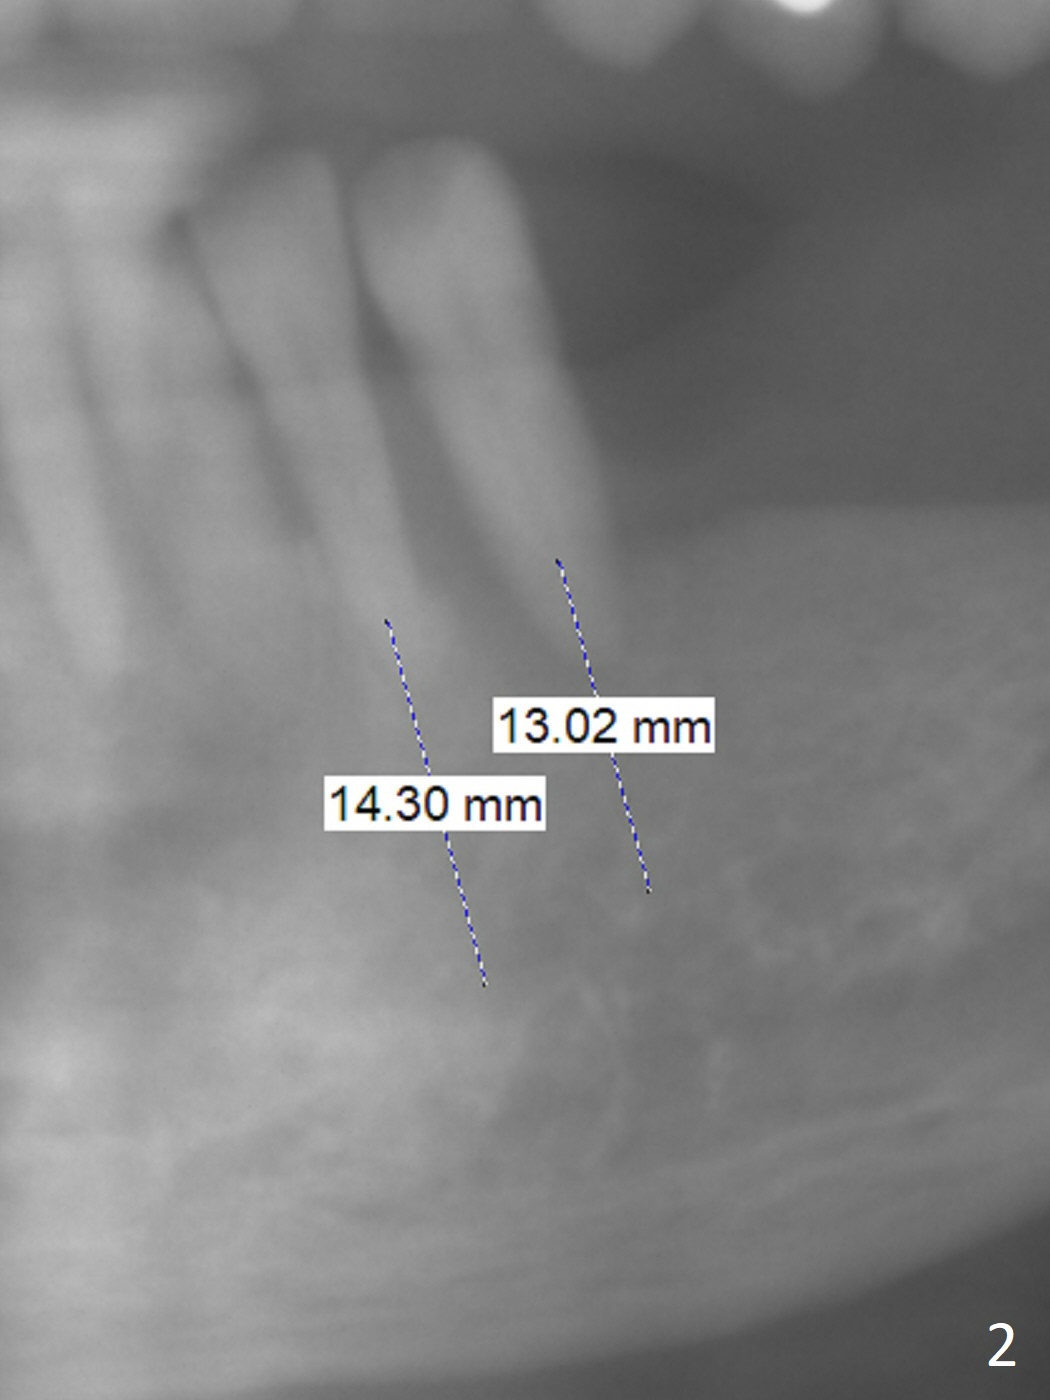

A 71-year-old woman is skinny with multiple missing teeth (Fig.1). Our final plan is to establish premolar occlusion. The first aim is to place implants at #22 and 23 with severe mobility and gingival recession (Fig.2). The latter is most likely due to traumatic occlusion from #10 implant crown. Pay attention to occlusion while an immediate provisional is being fabricated. After extraction, trajectory should be set up as shown by red lines in Fig.3. Initiate osteotomy in the middle of the sockets (buccolingually) and use the narrowest implants (2.5, 3.5 mm) to avoid the lingual plate perforation. Take preop photos to show #9,10 gingival recession.